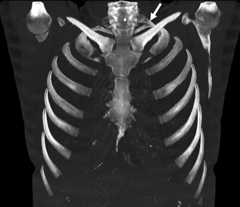

Hypoplastic rib prevalence was found as 10.27%. There were hypoplastic ribs in 115 (52.04%) cases, and their mean age was 52.67. In 2 cases, the first rib was hypoplastic; both were male and on the left side. In 113 cases (51 male, 62 female), the 12th ribs were hypoplastic. Ninety-eight cases had bilateral hypoplastic 12th rib, while 15 (7 on the right, 8 on the left) had unilateral (Table 5). The mean length of all hypoplastic 12th ribs was found to be 3.98 ± 1.58 cm on the left side and 4.00 ± 1.35 cm on the right (p > 0.05; Fig. 7).

Figure 7.Bilateral hypoplastic 12th rib.